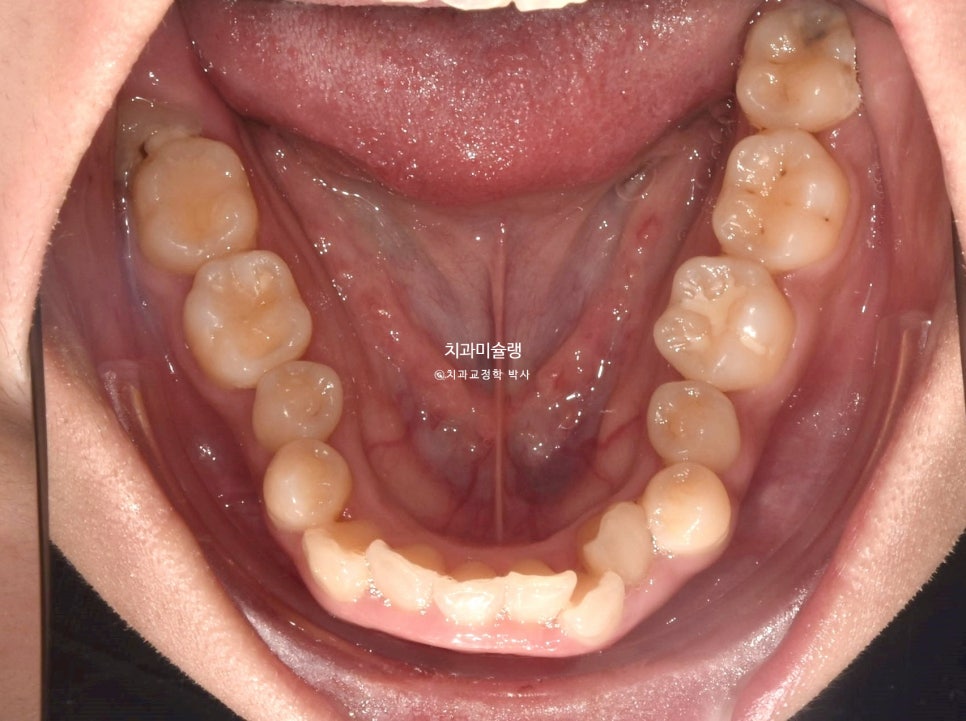

악궁이 소구치 부위가 안으로 쓰러져 찌그러진 모양입니다.

앞니뿐 아니라 어금니에도 여기저기 충치가 보입니다.

총생 (치아 삐뚤한 정도) 가 심하고 돌출감도 있어 작은어금니 4개 발치가 불가피한 상황입니다.